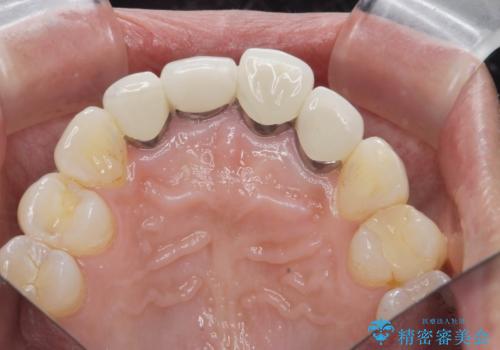

金属色の見える前歯 オールセラミックで審美治療

- 前歯のクラウンの見た目が不自然、歯の根元が見えたり金属色が気になるので改善したい、とセラミック治療を希望され来院されました。

歯肉の位置変化による審美障害を改善するため、オールセラミックジルコニアクラウンで再治療を行い審美性の改善を計画します。

- 52.8万円(ジルコニアクラウン×4・仮歯×4)費用は治療当時の料金となります

見た目が自然になり、色調も天然の歯とおなじような透明感のある色調が再現され、大変喜んでいただくことができました。